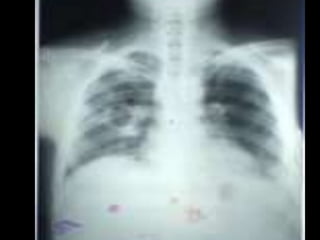

• C’est untéléthorax de face objectivant de multiples opacités de tonalité hydrique de taille et de formes variables intéressant les deux champs pulmonaires prédominant au niveau des bases, confluentes par endroits de plage homogène. • • L’index cardio thoracique ne peut être mesurer, les culs de sacs pleuraux sont libres et on note l’absence de lésions osseuses visibles • Conclusion : syndrome interstitiel et de comblement alvéolaire réalisant l’aspect en lâché de ballon évoquant des localisations secondaires. • Diagnostic différentiel : staphylococcie pleuro pulmonaire • CAT : TDM thoraco-abdominale, échographie abdomino-pelvienne et scintigraphie osseuse .Ce bilan d’extension a un double intérêt : celui de rechercher le néo primitif et celui d’essayer de déterminer d’autres atteintes